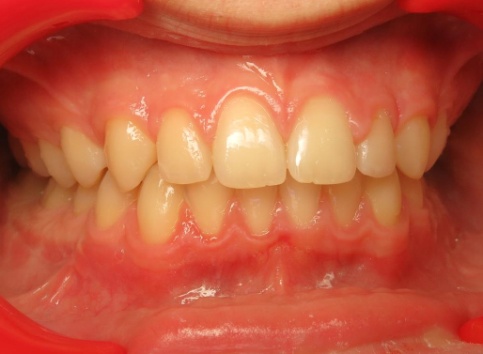

1 - Arcades dentaires avant-après

Les arcades dentaires montrent un décalage majeur de classe II, avec des incisives inférieures en position très reculée, venant directement au contact du palais. Cette configuration traduisait un déséquilibre squelettique important entre maxillaire et mandibule. Le traitement a consisté en une préparation orthodontique rigoureuse, suivie d’une chirurgie orthognathique permettant de repositionner les bases osseuses et de restaurer une occlusion fonctionnelle.